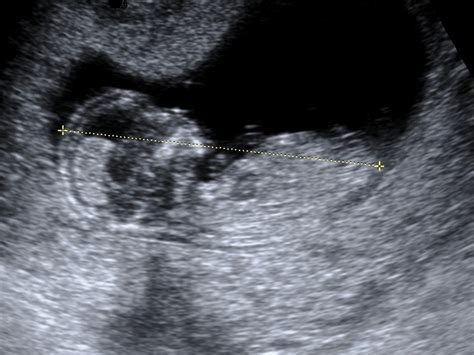

Kajenje med nosečnostjo neposredno vpliva na otrokov razvoj. Zaradi kajenja ima plod na voljo bistveno manj razpoložljivih hranil in kisika, oba pa sta ključnega pomena za njegov razvoj. Raziskave kažejo, da imajo otroci, ki so bili med nosečnostjo izpostavljeni dimu, zaradi manjšega dostopa do hranil in kisika pogosteje nižjo porodno težo. A to ni edina negativna posledica.

Prenehanje kajenja pozitivno vpliva tudi na zdravje žilne mreže, vključno s posteljico. Bolj zdrave žile matere omogočajo, da posteljica bolje opravlja svojo ključno vlogo pri prenašanju kisika in hranilnih snovi do ploda.

- Zmanjšana rast še nerojenega otroka in posledično nižja porodna teža.